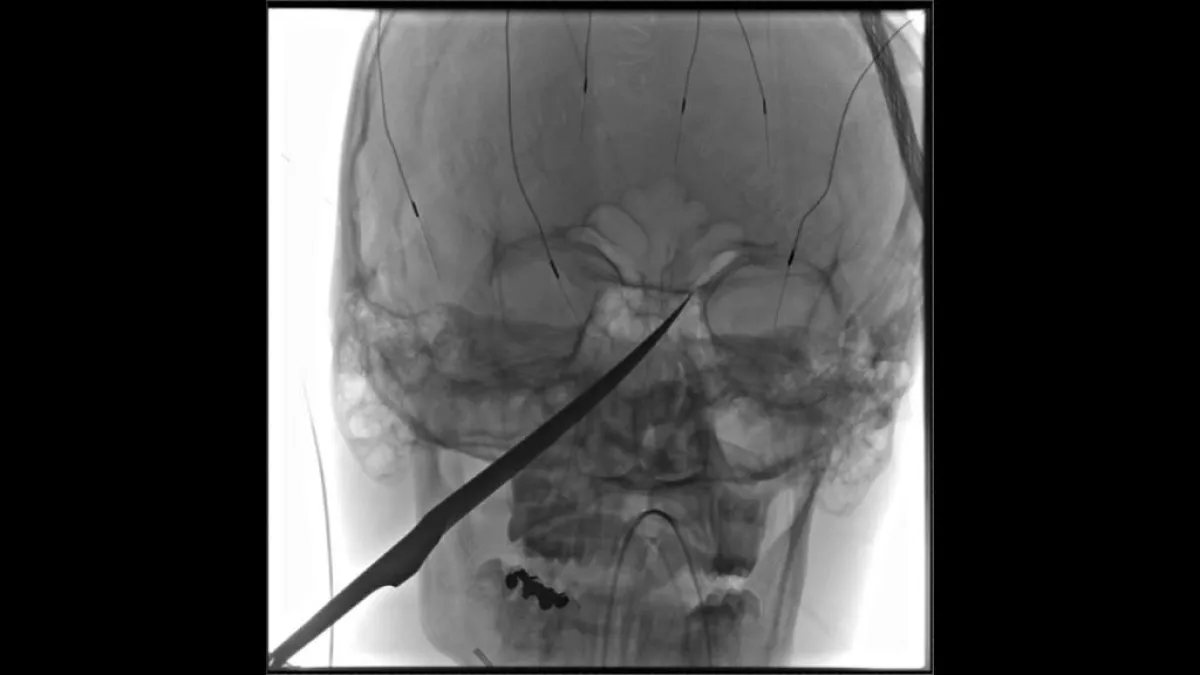

معجزة طبية جديدة، قام بها عدد من الأطباء في ولاية «كانساس» التي تقع في الغرب الأوسط للولايات المتحدة الأمريكية. بعدما تمكنوا بأعجوبة كبيرة من إنقاذ حياة الفتى المراهق «إيلي غريغ»، البالغ من العمر 15 عاماً. والذي كان قد وصل إلى المستشفى وهناك سكين بطول 25 سنتيمتراً يخرج من جمجمته. بحادثة مروعة تعرض لها في الأيام الماضية.

وتابعت «فوكس نيوز»، أنه تم نقل «إيلي»، إلى مستشفى «ميرسي» للأطفال في الولاية. وعلى الفور سارع الأطباء لحظة وصوله إلى إجراء الإسعافات اللازمة له. ولأن الأطباء كانوا قلقين من احتمالية تلف «الشريان السباتي» في دماغ الفتى، مما سيؤدي إلى الإصابة بالسكتة الدماغية أو أضرار جسيمة أخرى في الدماغ. قرروا على الفور نقله إلى النظام الصحي بجامعة كانساس.

وبالفعل تم نقله إلى مستشفى الجامعة، وهناك أمضى الأطباء الساعات الـ24 التالية، في علاج الفتى الأمريكي، وبذلوا كل ما لديهم لإنقاذ حياته. وبالفعل استطاعوا أخيراً إخراج السكين من جمجمته. ويخضع «إيلي» في الوقت الحالي للعلاج بالمضادات الحيوية واللقاح ضد الكزاز الـ«تيتانوس». وعلى جانب آخر، تم تحذيره وتحذير والدته «جيمي راسل» من الاقتراب من أي أدوات حادة على الإطلاق.